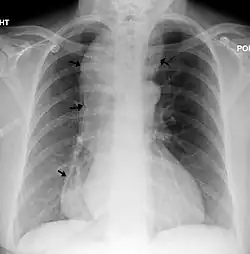

| A chest X-ray showing achalasia (arrows point to the outline of the massively dilated esophagus) | |

End-stage achalasia, typified by a massively dilated and tortuous oesophagus, may occur in patients previously treated but where further dilatation or myotomy fails to relieve dysphagia or prevent nutritional deterioration, and esophagectomy may be the only option.[16]